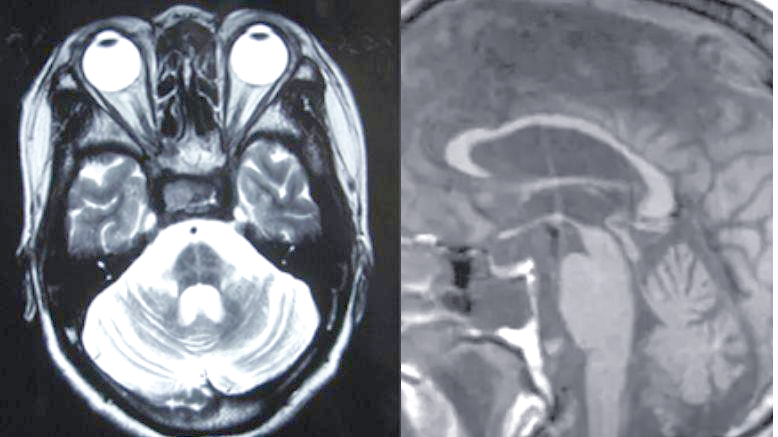

20240414_figure 6.18 mega cisterna magn

大枕大池:常见解剖变异

大枕大池及其鉴别诊断详解